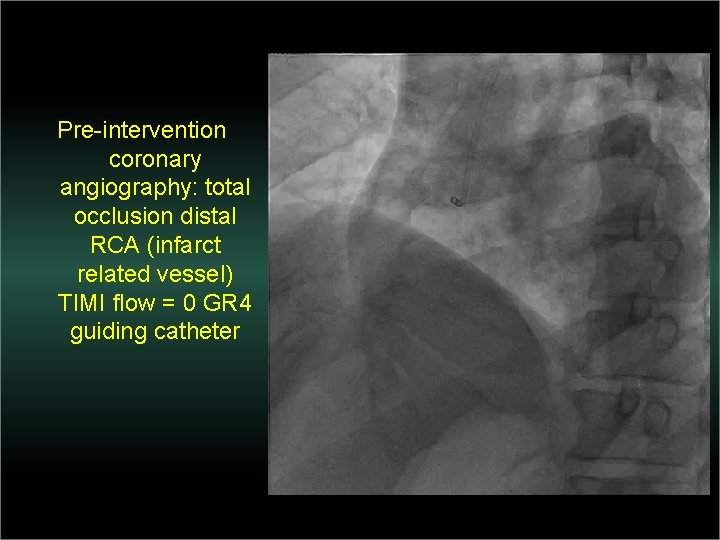

Transradial Interventions Difficult Anatomic Substrate Challenges and Solutions